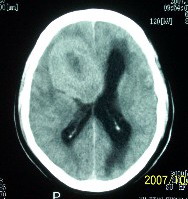

f    29岁   头闷  头晕1月余

这么大,鞍上压迫那么厉害,梗阻也比较重没有视力及其他症状吗?从肿瘤本身表现看,支持考虑颅底脑膜瘤

肿瘤长入侧脑室,侧脑室明显扩大, 病灶边界清楚,其内可见低密度坏死区,中枢神经细胞瘤?室管膜瘤?

右额叶底部巨大等低混杂密度肿块,边界清楚,周围水肿轻度,明显占位效应。蝶鞍扩大,部分骨质破坏。

考虑脑膜瘤,建议增强扫描进一步检查。

蝶鞍受压吸收,可以排除室管膜瘤。肿瘤最大层面不在蝶鞍可以排除垂体瘤。支持脑膜瘤